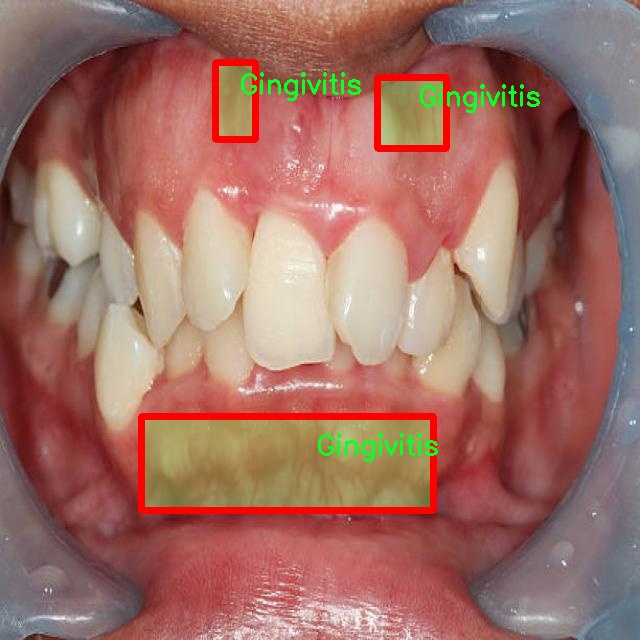

图片效果

在这里插入图片描述

在本研究中,我们使用了名为“unbeknownst to man”的数据集,旨在改进YOLOv8-seg的口腔疾病图像分割系统。该数据集专注于口腔健康领域,涵盖了四种主要的口腔疾病类别,分别是龋齿(Caries)、牙龈炎(Gingivitis)、牙齿变色(Tooth Discoloration)和溃疡(Ulcer)。这些类别的选择不仅反映了口腔疾病的多样性,也为我们提供了一个全面的视角,以便更好地理解和分析这些疾病的表现形式及其在图像中的特征。

数据集中的每个类别都包含大量高质量的图像,这些图像经过精心标注,确保了每个样本的准确性和一致性。龋齿作为最常见的口腔疾病之一,其图像展示了不同阶段的龋齿发展,从初期的微小白斑到严重的牙体损坏,图像中清晰的细节为模型训练提供了丰富的信息。牙龈炎则通过展示红肿、出血等症状,帮助模型学习如何识别和分割出受影响的牙龈区域。牙齿变色的图像则展示了因多种因素导致的牙齿色泽变化,这些变化可能是由于饮食、生活习惯或口腔卫生不良等原因引起的。最后,溃疡的图像则提供了对口腔内病变的直观表现,通常伴随着疼痛和不适,这类图像的标注对于识别和分割至关重要。